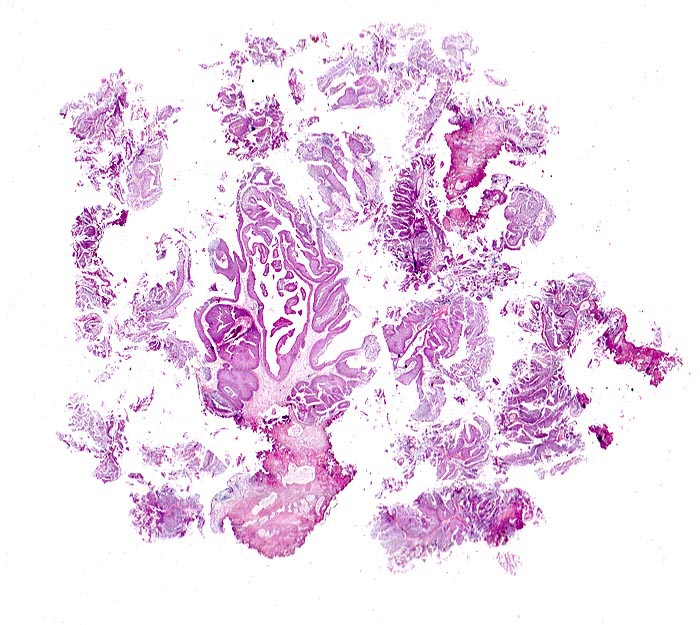

Morphologische Merkmale:

• Transurethrale Resektate von Harnblasenschleimhaut mit papillärem Tumor.

• Das neoplastische Urothel bildet fingerförmige, teils miteinander verschmelzende Papillen mit schmalen fibrovaskulären Stromastielen.

• Das neoplastische Urothel ist verbreitert (meist mehr als 7 Zellagen).

• Scharfe Grenze zwischen Epithel und subepithelialem Stroma (keine Invasion).